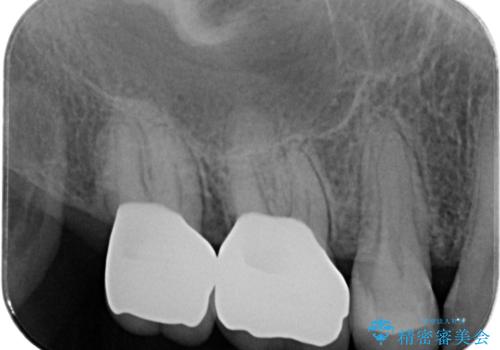

歯周組織検査・X線検査の結果、中等度の歯周病であることがわかりました。

歯周ポケットの除去を歯周外科により行ったのち精度が高く清掃のしやすいセラミック治療による再補綴を行います。